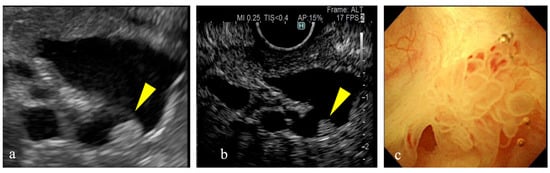

Figure 2. A mural nodule exhibiting enhancement. (a) Conventional B-mode imaging shows a hyperechoic mural nodule inside a cyst (yellow arrow). (b) A contrast-enhanced image shows homogeneous enhancement in the mural nodule (yellow arrow). (c) A papillary mural nodule is observed during peroral pancreatoscopy.